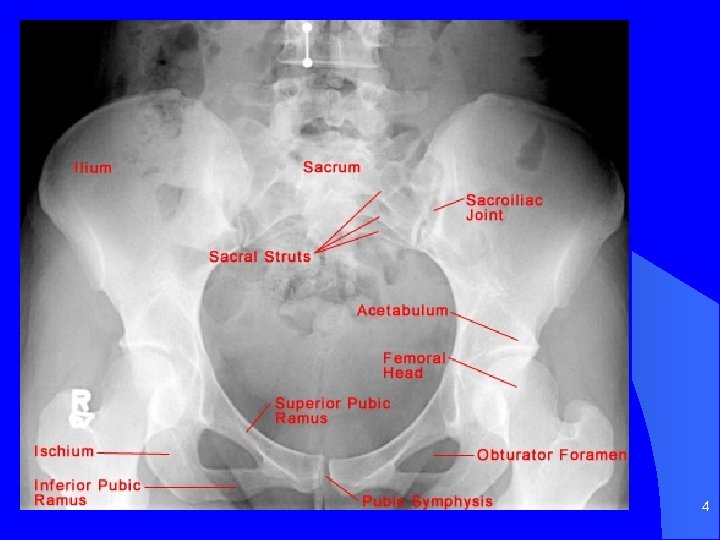

4